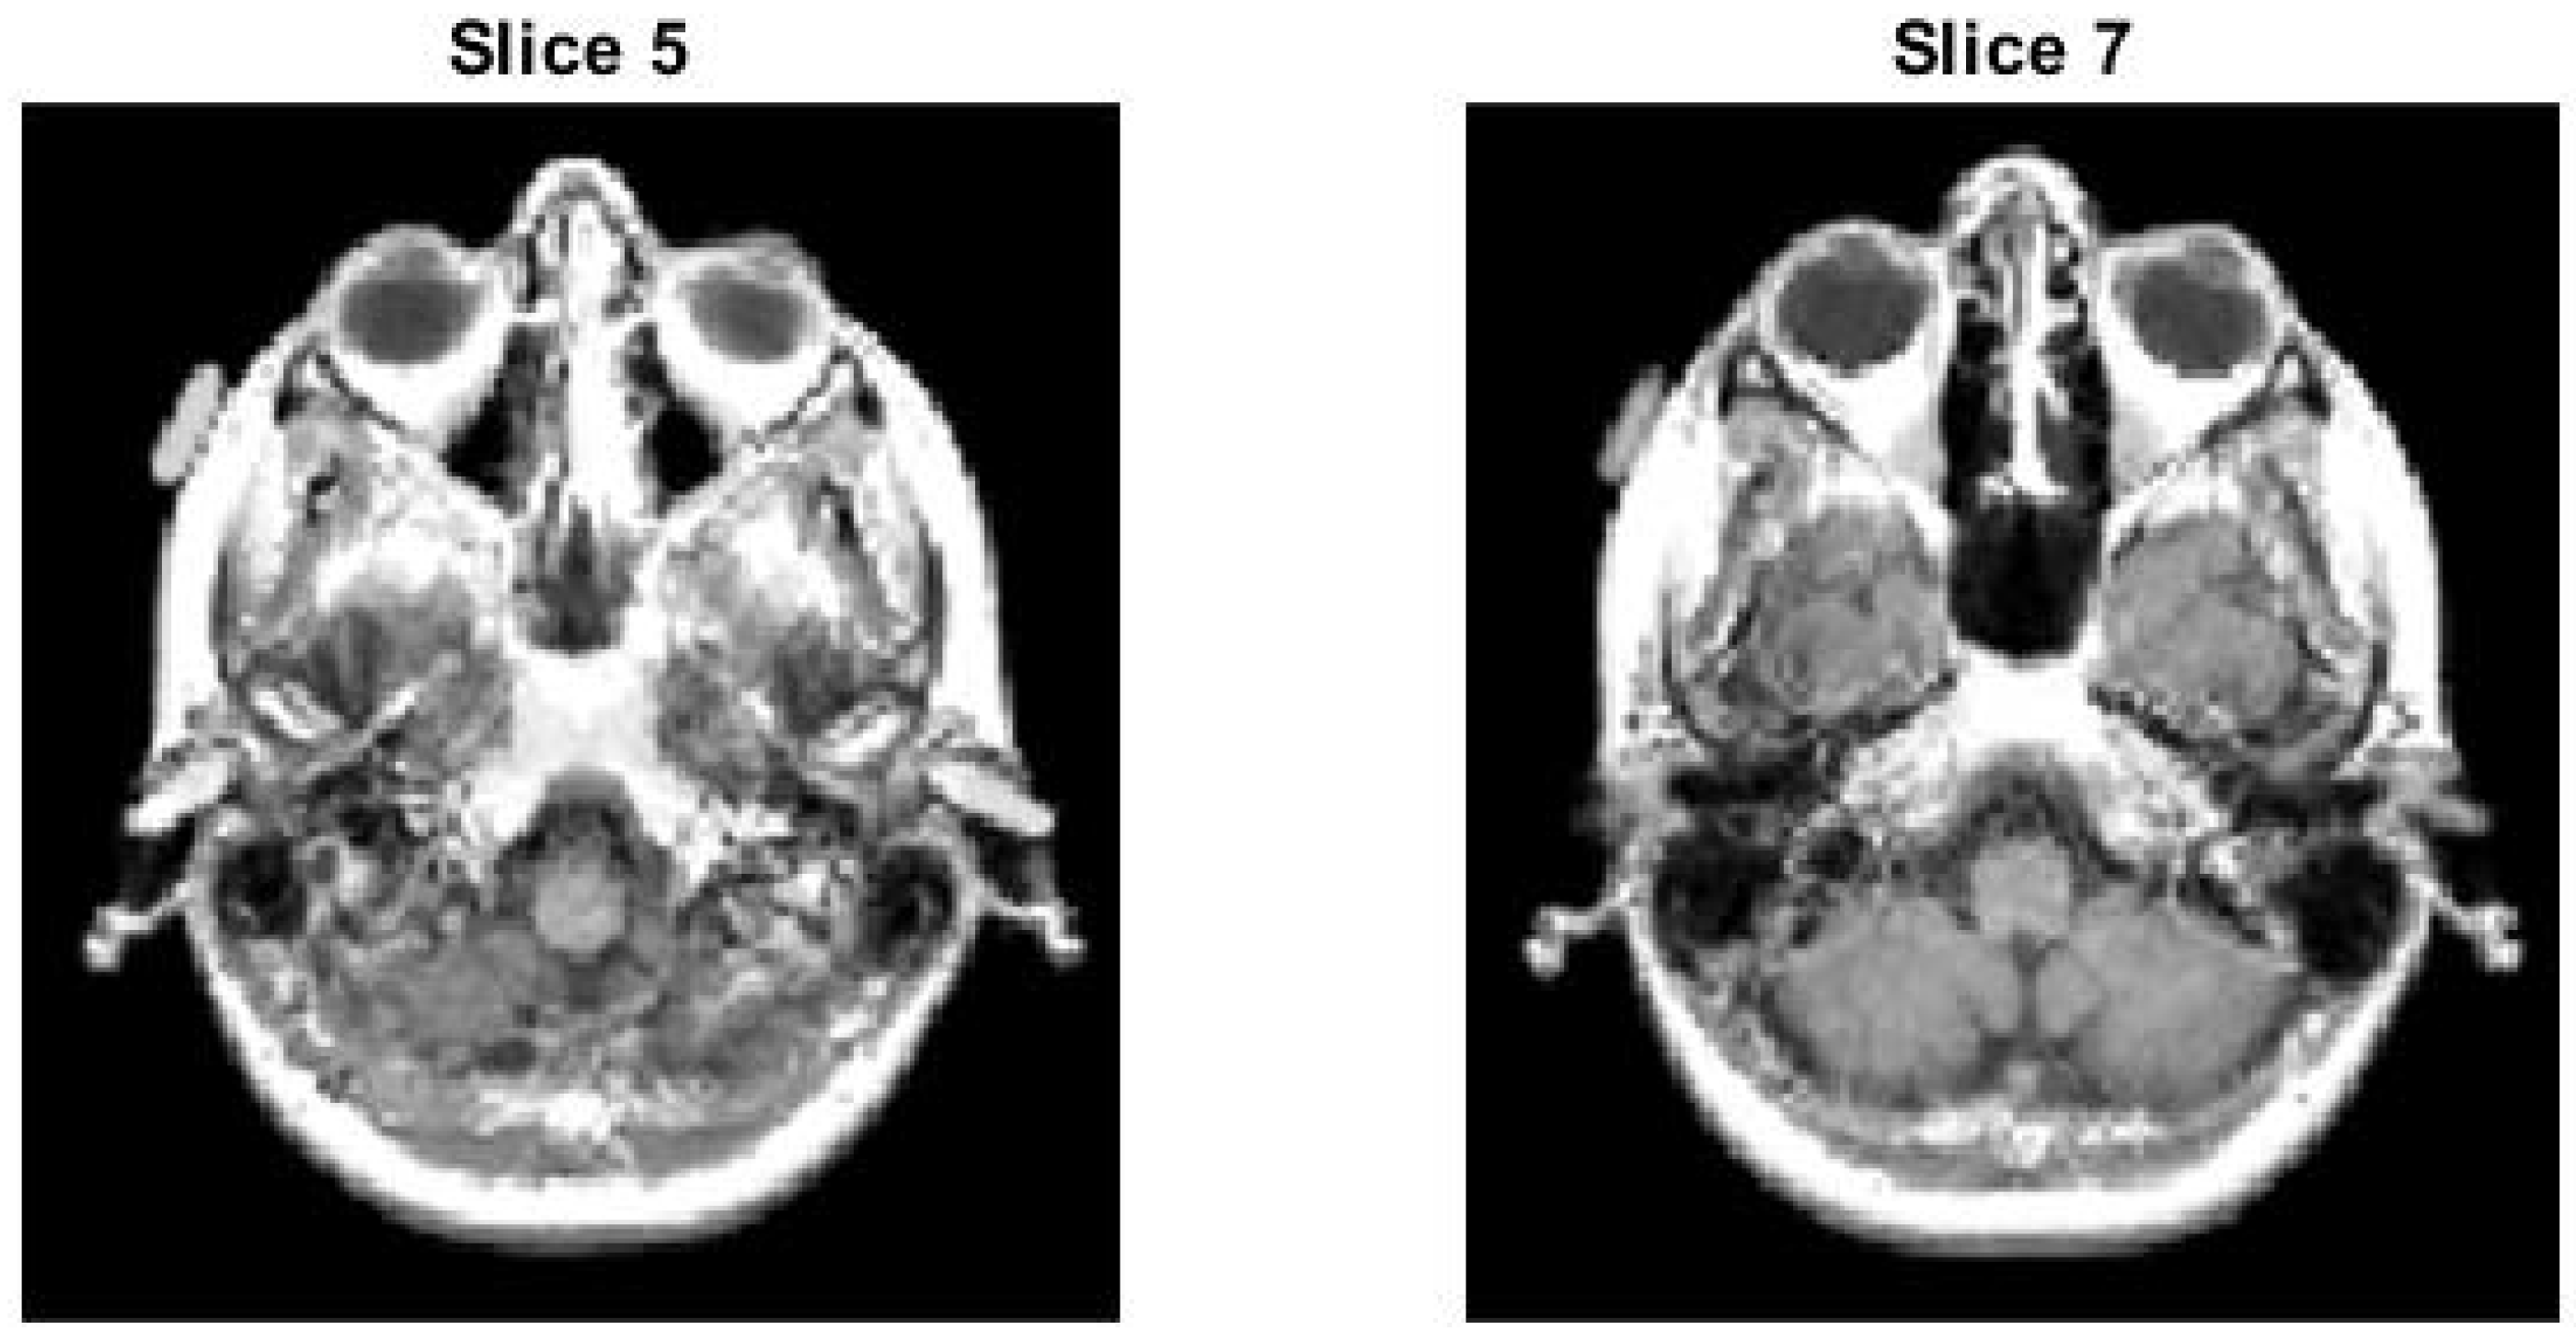

- Test image 1 is a 3D MRI scan of a portion of a skull, encoded in 8-bit unsigned integer (uint8) format.

4.1. Test Image 1

4.1.1. Whole Test Image 1

4.1.2. Slice 5 of Test Image 1